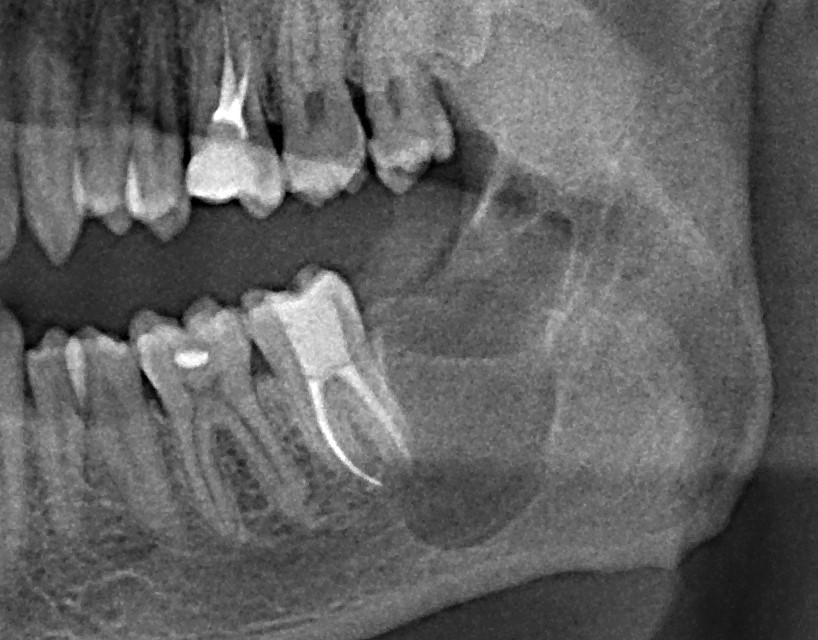

Это мой самый любимый и тщательно подготовленный проект — семинар по немедленной имплантации. Он уже дважды был в Москве, и однажды — в Нижнем Новгороде. На этот раз, мы проводим его совместно с компанией APEX в Санкт-Петербурге, и посвящен он будет… догадайтесь с трех раз?))) Через фокус немедленной имплантации будут рассмотрены различные имплантационные системы, операции остеопластики, синуслифтинга, удаления зубов и превентивной аугментации лунок.

Ключевой семинар по использованию биоматериалов в имплантологии, остеопластических операциях, мукогингивальной хирургии и хирургической пародонтологии. Я спланировал семинар как ответ на главный вопрос: «Почему нам вообще нужны биоматериалы, и можем ли мы без них обойтись?» В ходе семинара подробно рассмотрены основные методики регенерации костной ткани, начиная от пластики крупными аутокостными фрагментами, заканчивая направленной костной регенерацией, с имплантами или без.

Как видно из названия, семинар посвящен самой частой и распространенной хирургической операции в мире — удалению зубов. Это новое мероприятие в моем графике, мы проводим его совместно с IDA (International Dentistry Association). В ходе семинара будут рассмотрены различные методики удаления зубов, в том числе удаление ретинированных зубов мудрости, сверхкомплектных зубов, а также операции, включающие в себя эту процедуру: немедленная имплантация и превентивная аугментация лунок.